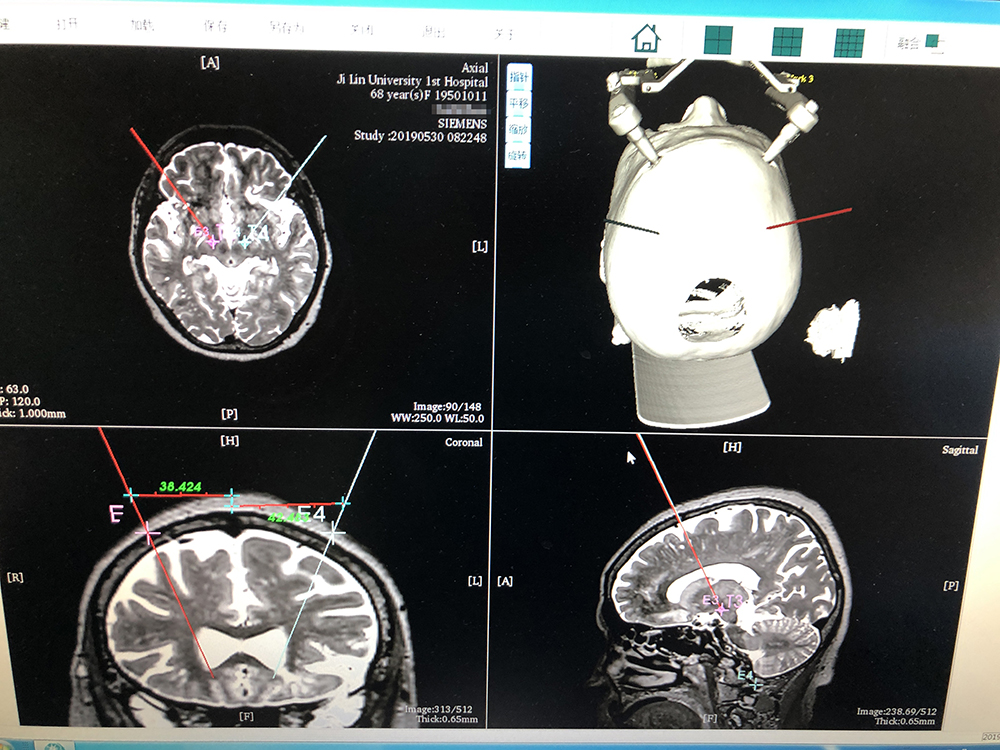

術前,邱吉慶教授借助“睿米”神經外科手術機器人配套軟件,為患者制定雙側 STN 核團植入電極的手術路徑規劃。

借助“睿米”軟件制定手術規劃